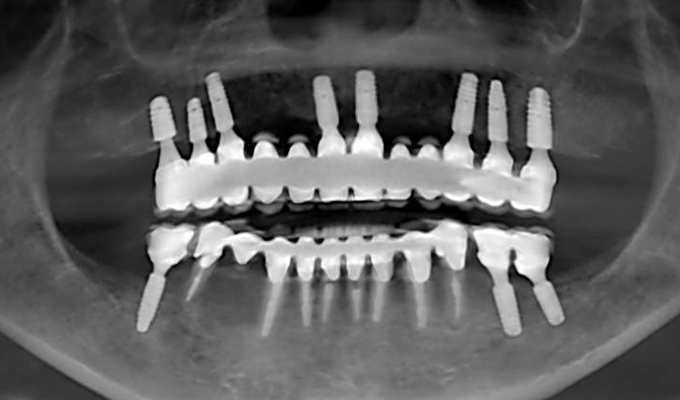

case1インプラントとメタルボンドブリッジの症例

初診時(2010年)

初回メンテナンス時(2014年)

最新メンテナンス時(2024年)

- 初診時の年齢

- 60代女性(2010年)

- 主訴

- ちゃんと咬めるようになりたい。最近孫が生まれたから一緒に歌ったりしたいけど、今は歌うこともできないから・・・・。と

- 治療内容

- 5年ほど前に入れ歯を作ったそうですが合わなかったので使用してなかったせいか前歯がグラグラになっていて今にも抜けそうな状態でした。

保存が難しい歯を抜歯し、上はインプラント8本、下は奥歯にインプラント4本埋入しました。

補綴は変色しないメタルボンドを選択されたので治療完了して11年経過してもとてもきれいな状態で維持されています。

初診時にお話しされていたお孫さんも中学2年生になったそうで、歯の治療をしたおかげで充実した毎日が送れてます、とメンテナンス時もいつも嬉しそうにされています。